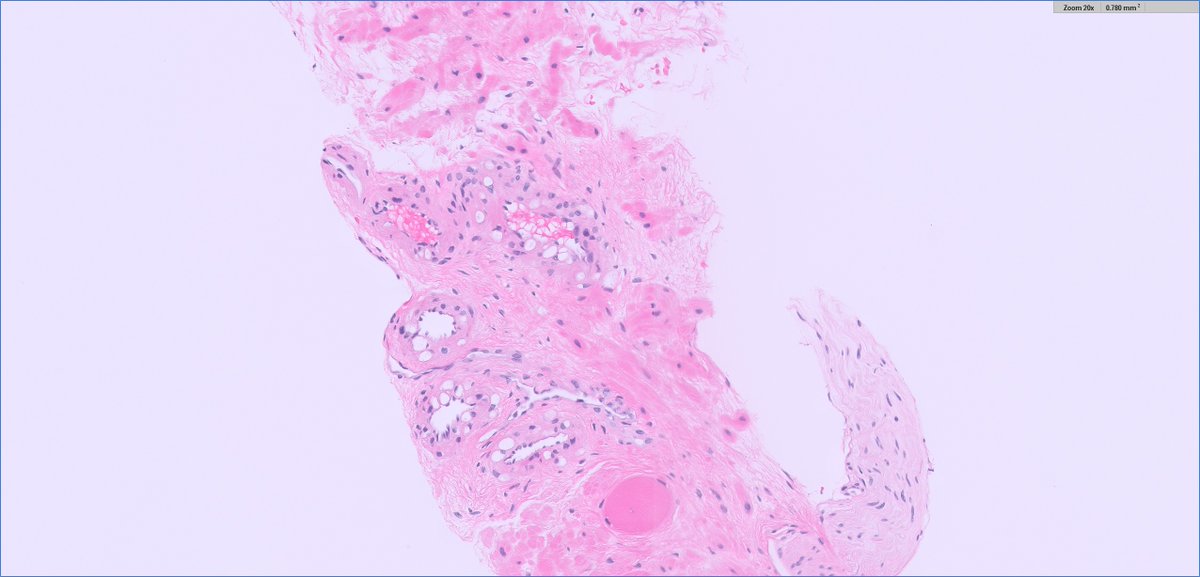

all good DDx! this was perhaps indeed #TooCloseToDiagnose but Samson W. Fine, MD was closest this was hemangioma-like foci in a low grade clear cell RCC (lower power you can👁️more solid tumor cell aggregates) ✔️paired CA9 #IHCpath (note just how many sneaky tumor cells there are!)

Daniel Berney Michelle_Hirsch (Donovan) Diagnosis of CIS in fragmented TURBT specimens is often difficult and subjective. Only CIS away from papillary tumour should warrant categorisation as very high risk (potential upfront cystectomy). Have a high threshold for diagnosing CIS in TURBT specimens.